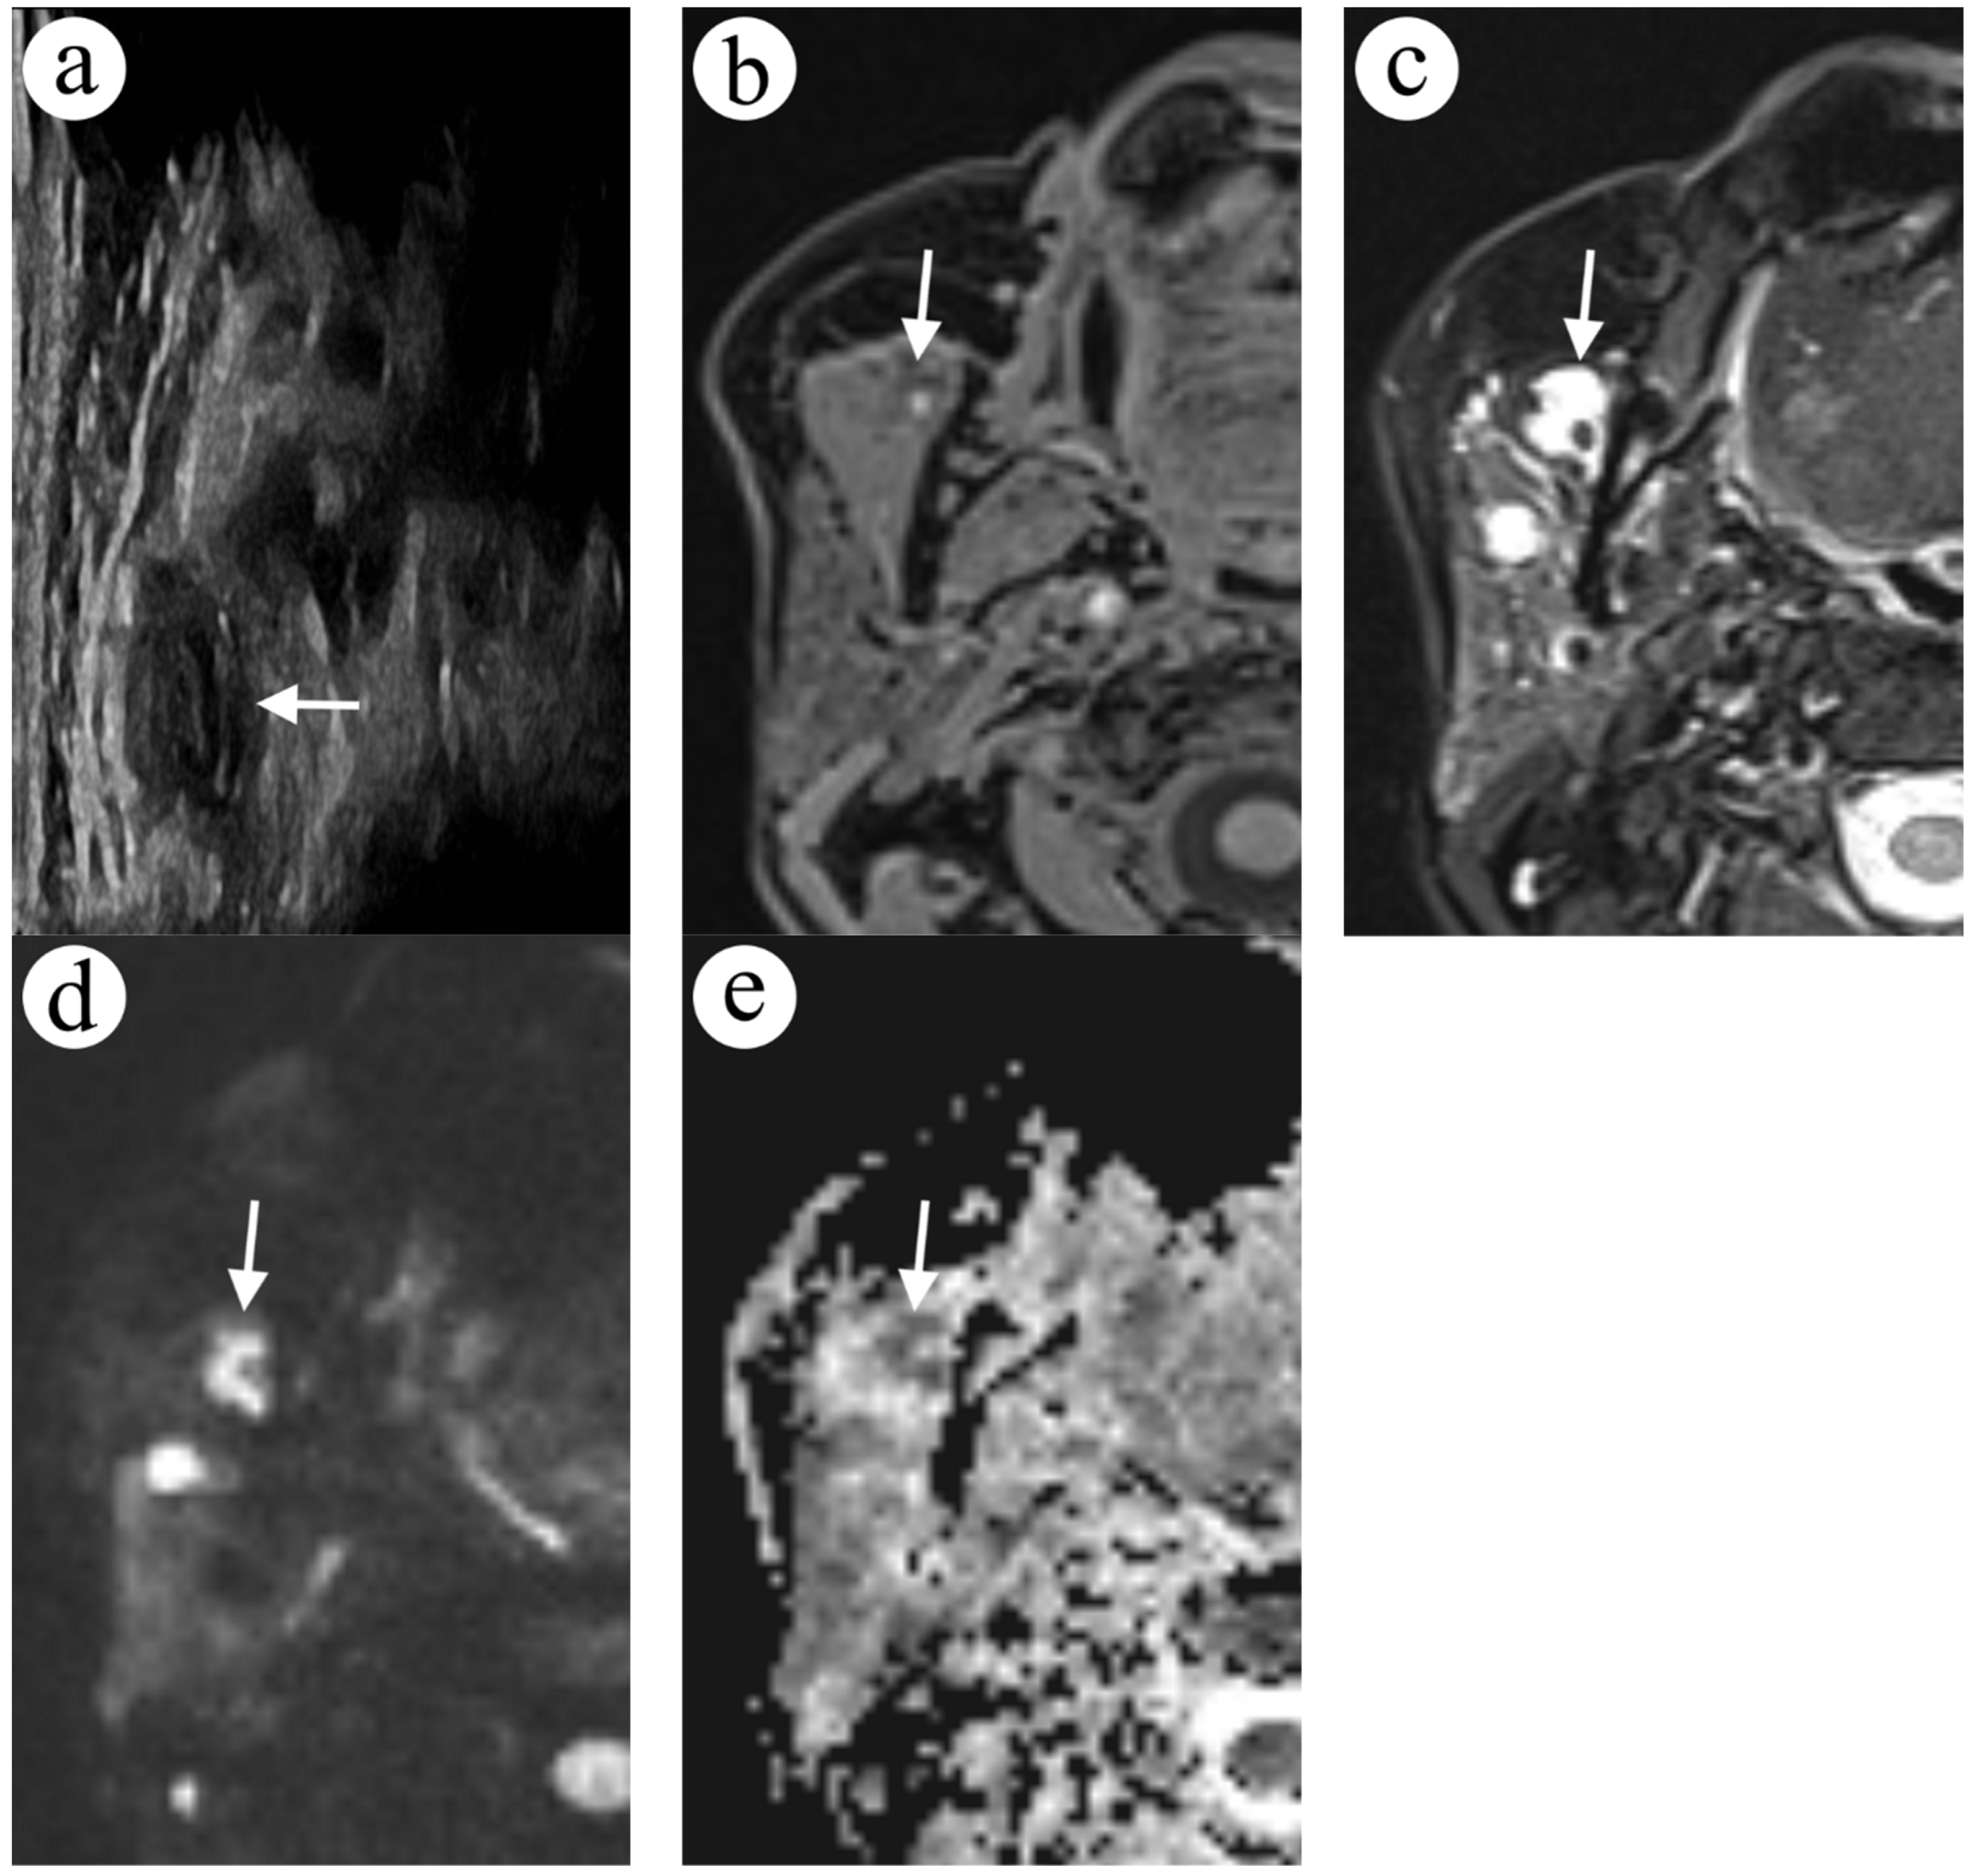

2.2. Case 2